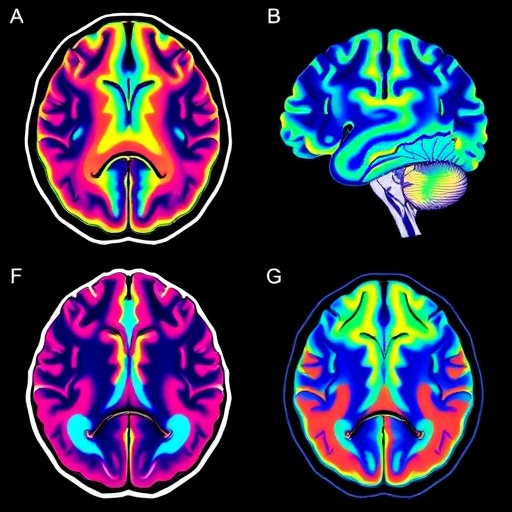

Utilizing state-of-the-art fetal magnetic resonance imaging (MRI) protocols, the research team embarked on a meticulous longitudinal examination of brain structural evolution during critical gestational windows. Unlike previous cross-sectional analyses, this approach allowed for the dynamic mapping of the volumetric and morphological growth patterns of essential brain nuclei and cortical regions from mid-gestation until term. The continuous imaging series generated a high-resolution atlas delineating normative trajectories, surpassing prior attempts limited by smaller cohorts or narrower temporal scopes.

The technical rigor of this study was exemplified by the application of advanced motion correction algorithms and sophisticated brain tissue segmentation techniques, overcoming significant challenges inherent to fetal imaging such as spontaneous fetal movements and variable in utero positioning. Employing novel machine learning models trained on annotated datasets, the authors achieved automated delineation of subcortical structures with exceptional accuracy, enabling reproducible quantification of neuroanatomical volumes essential for growth curve construction.

The longitudinal data illuminated differential growth rates among diverse brain regions, revealing nuanced patterns such as the accelerated volumetric expansion of the hippocampus and cerebellum relative to cortical areas during the late second and third trimesters. These findings underscore the heterochronous nature of fetal brain maturation and emphasize the importance of region-specific normative data to discern typical from aberrant developmental courses.